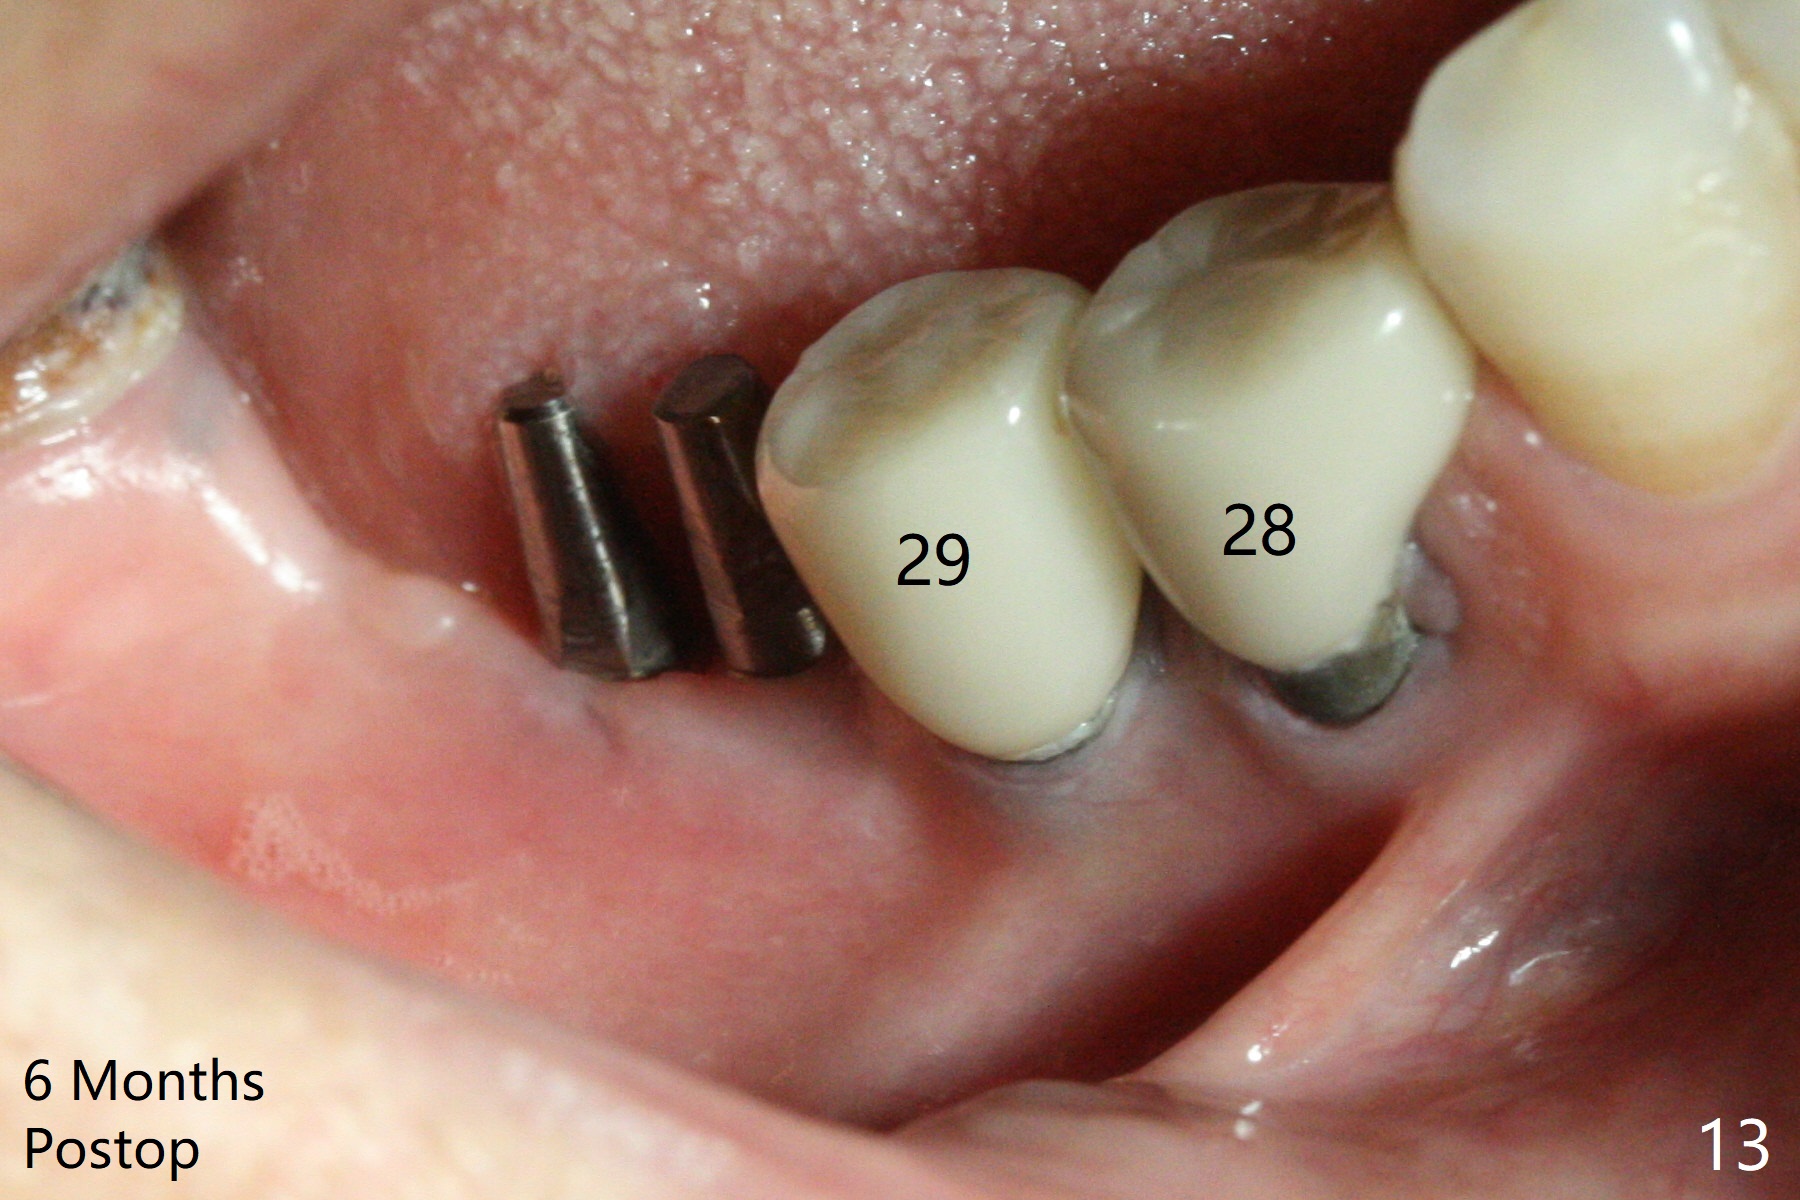

Two of 2.5 mm 1-Piece Implants M

The edentulous ridge at #30 is narrow (Fig.1). After ridge reduction, osteotomy is initiated with 1.2 mm drill for 10 mm; the mesial osteotomy is to be changed (Fig.2 red line). Using a 1.2 mm drill placed in the distal osteotomy (Fig.3 D), the mesial osteotomy changes in trajectory with subsequent placement of a 2.5x10(4) mm 1-piece implant. Since the mesial implant is high in occlusion, the cuff of the distal implant is changed to be 2 mm (Fig.4 (shorter black line)). Panoramic X-ray is taken to show no violation of the Inferior Alveolar Canal (Fig.5 red dashed line). These two 1-piece implants are slightly lingually placed (Fig.6). The crestal bone around the implants resorbs without thread exposure 5 months postop (Fig.7). Impression is taken for a splinted crown (Fig.8-12). There is no metal show around the 2.5 mm 1-piece implants 6 months postop (advantage) vs. that at #28 and 29 (Fig.13). Bitewing is taken post cementation to determine whether residual cement is present (Fig.14). There is periodic swelling and pain in the lower right quadrant 2 years post cementation (Fig.15). In fact periimplantitis appears to have developed at #28 (Fig.16) with loss of the buccal bone (Fig.17,18). The buccal bone loss is less at #29 (Fig.19) and #20 (Fig.23) and no at #30 mesial and distal implants (Fig.20,21). A much smaller implant will be placed lingually at #28 immediate (Fig.24,25).